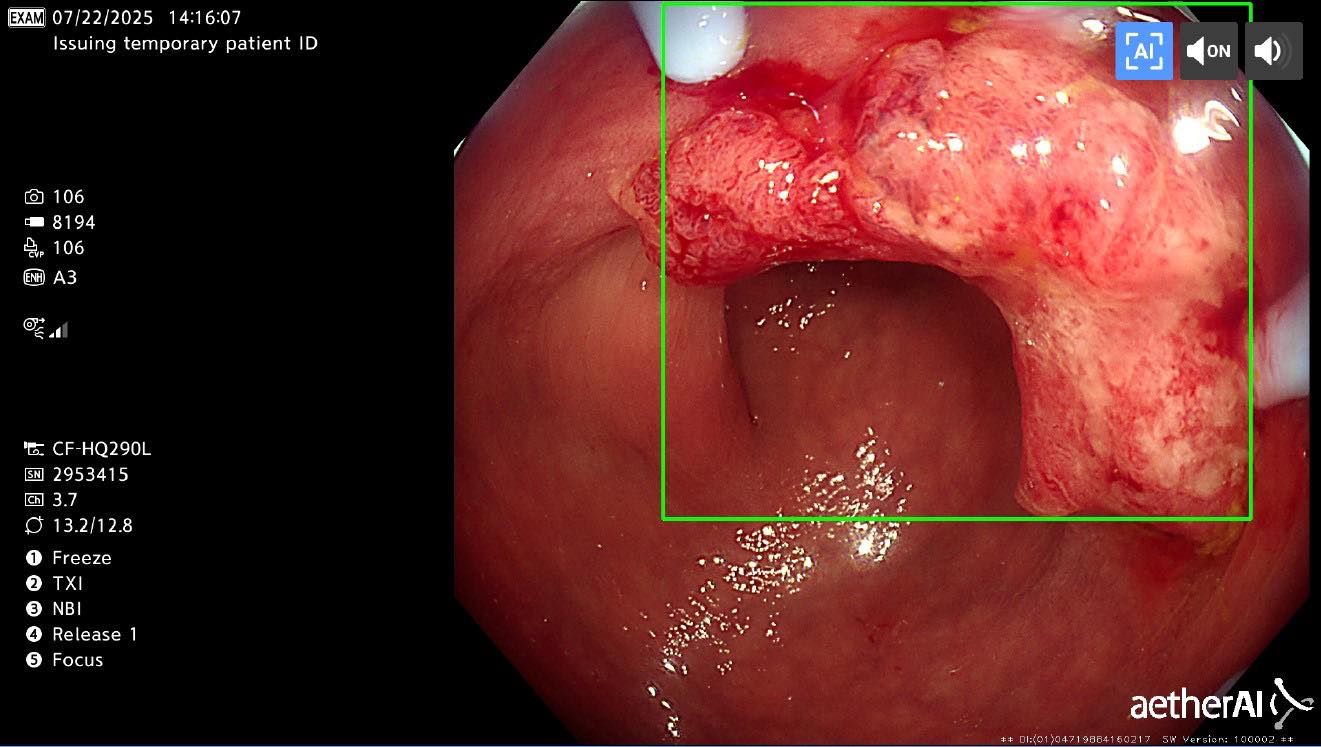

前幾天,我替一位只有 28 歲的病人做大腸鏡

前幾天,我替一位只有 28 歲的病人做大腸鏡,他原本只是順便檢查,事前沒有任何症狀,結果居然確診是大腸癌。當我告訴他時,他沉默了很久,眼神裡除了震驚,還有一種「怎麼可能是我」的無助,那份沉重,讓人真的喘不過氣。